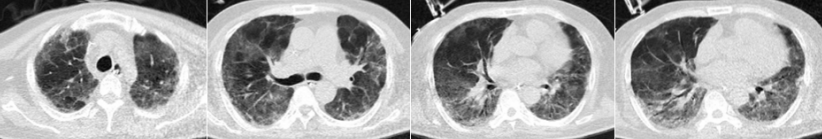

发病第16天(2022年12月26日)复查胸部CT发现病变加重。

患者2022年12月26日胸部CT